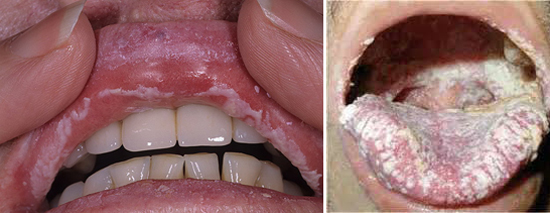

Молочница: симптомы во рту

Молочница ротовой полости – распространенное заболевание в любом возрасте.

У пожилых людей, кандидоз во рту встречается довольно часто. Связано это с использованием протезов. Нередко молочница во рту наблюдается у беременных женщин. На фоне сниженного иммунитета и гормонального сбоя, грибки с легкостью распространяются и паразитируют на слизистой ротовой полости.

Симптоматика кандидоза во рту:

Отек;

- Появление покраснений;

- Чрезмерная сухость ротовой полости;

- Белый налет на слизистой.

При отсутствии лечения, налет становится более явный, образуя консистенцию похожую на хлопья. Появляется боль при глотании, покраснения и заеды в уголках губ, жжение и постоянный зуд в ротовой полости.

Диагностируется заболевание при визуальном осмотре. В качестве подтверждения диагноза, врач направит сдать анализ – биоматериалом выступает в данном случае налет, который легко отделяется.

Симптомы молочницы при ВИЧ

Кандидоз у ВИЧ положительных пациентов – распространенное заболевание.

Главную роль в распространении Кандиды играет сниженный иммунитет. Чаще всего наблюдается у людей с вирусом иммунодефицита молочница ротовой полости.

У пациентов со СПИДом, грибок распространяется и паразитирует намного быстрее. Поражаются внутренние органы и появляются проблемы с пищеварительным трактом из-за отечности слизистой.